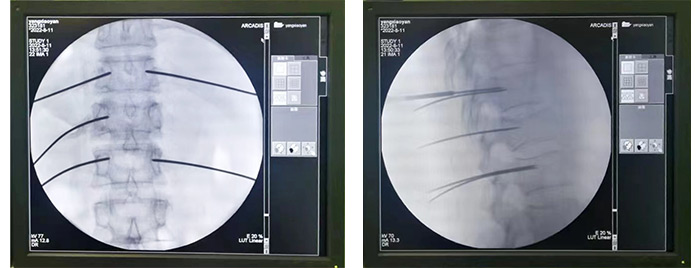

术中机器人定位

术中导针规划

术中置钉

第二天,尚军主任、孟磊医生手术团队在“天玑”骨科机器人定位下,通过3D图像扫描规划手术中椎弓根螺钉的进钉点、置钉方向以及置钉深度。根据机器人系统导航,通过机械臂定位,切开约2cm切口进行精准置钉,保障神经安全和手术的有效性,所有操作一步到位。最后C型臂透视检查骨折复位,脊柱生理序列恢复满意,内固定物位置良好。